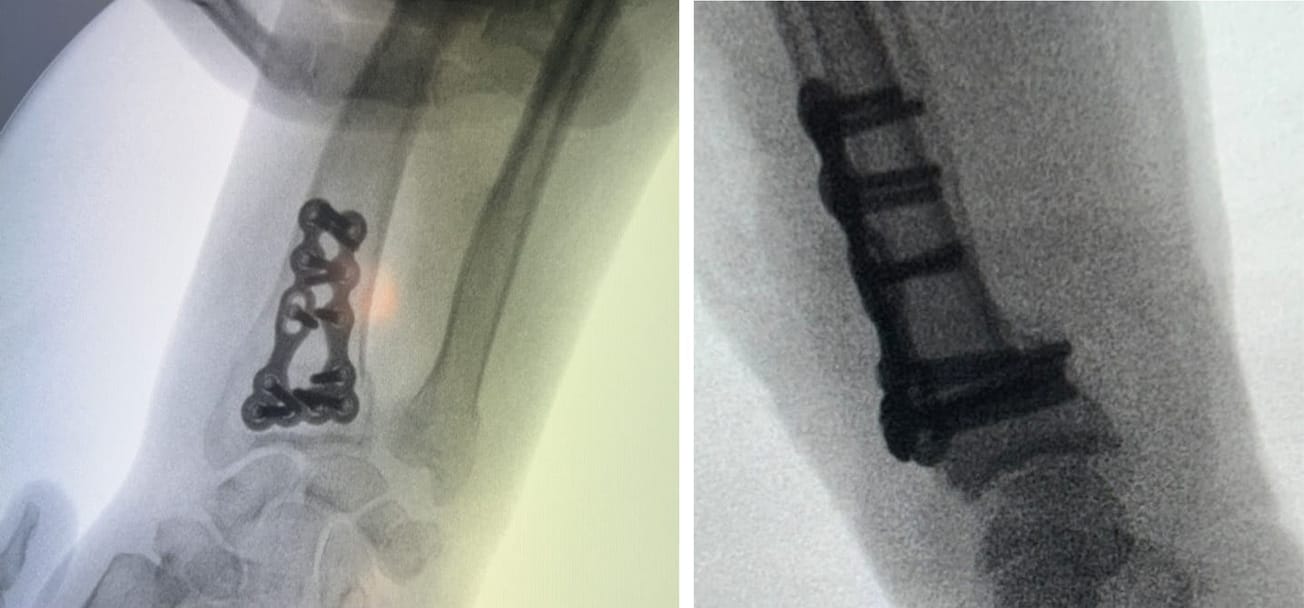

Technique Fracture à déplacement dorsal du radius et plaque dorsale , Philippe Pasquier Clinique de Montier-la-Celle, 10120 Saint-André-les-Vergers, France 🖂 p.pasquier@centre-main.com , Laurence Darbeley Clinique de Montier-la-Celle, 10120 Saint-André-les-Vergers, France N°335 - Juin / Juillet 2024 ● 11 min de lecture